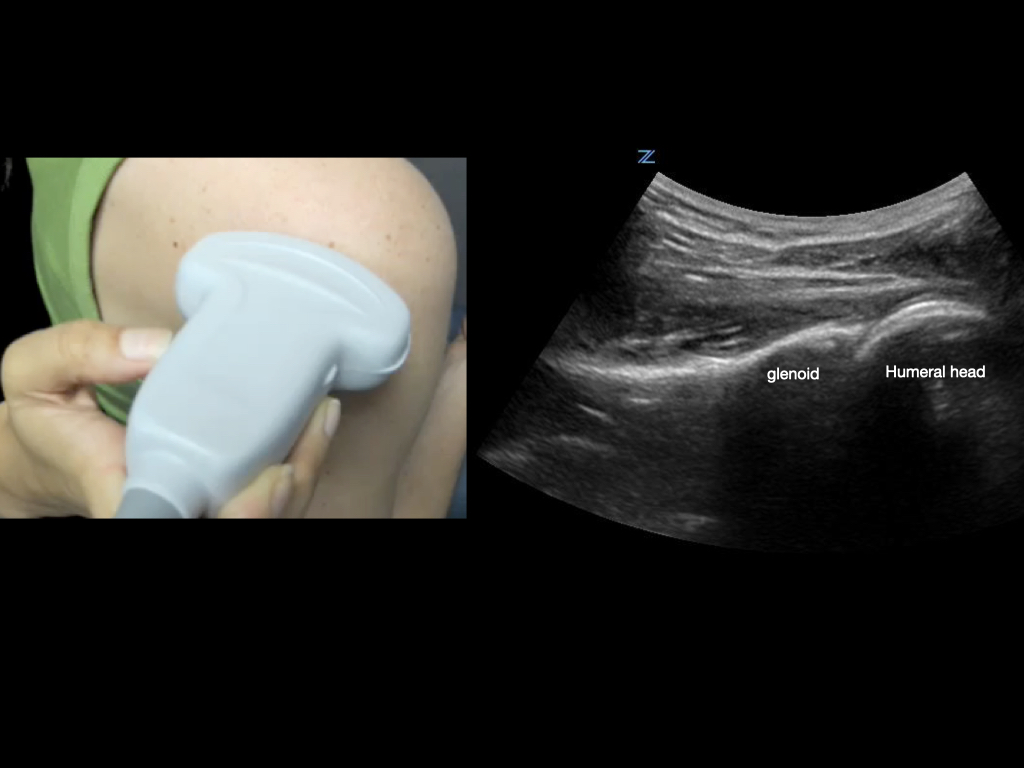

To best view the shoulder joint, consider using a curvilinear transducer. Align the transducer parallel and just inferior to the scapular spine, and slide the transducer out laterally until you are centered on the humeral head and glenoid.

Figure 4.

Transducer orientation when scanning the glenohumeral joint.

Take advantage of dynamic exams. For example, observe tendons moving through their range of motion; have the shoulder internally and externally rotate to observe the humeral head in the glenoid when evaluating for dislocation, etc.

Posterior shoulder internal and external rotation. This view (corresponding to Figure 4) shows the posterior humeral head rotating in the glenoid, confirming shoulder reduction, and demonstrating the rotator cuff tendon in motion.